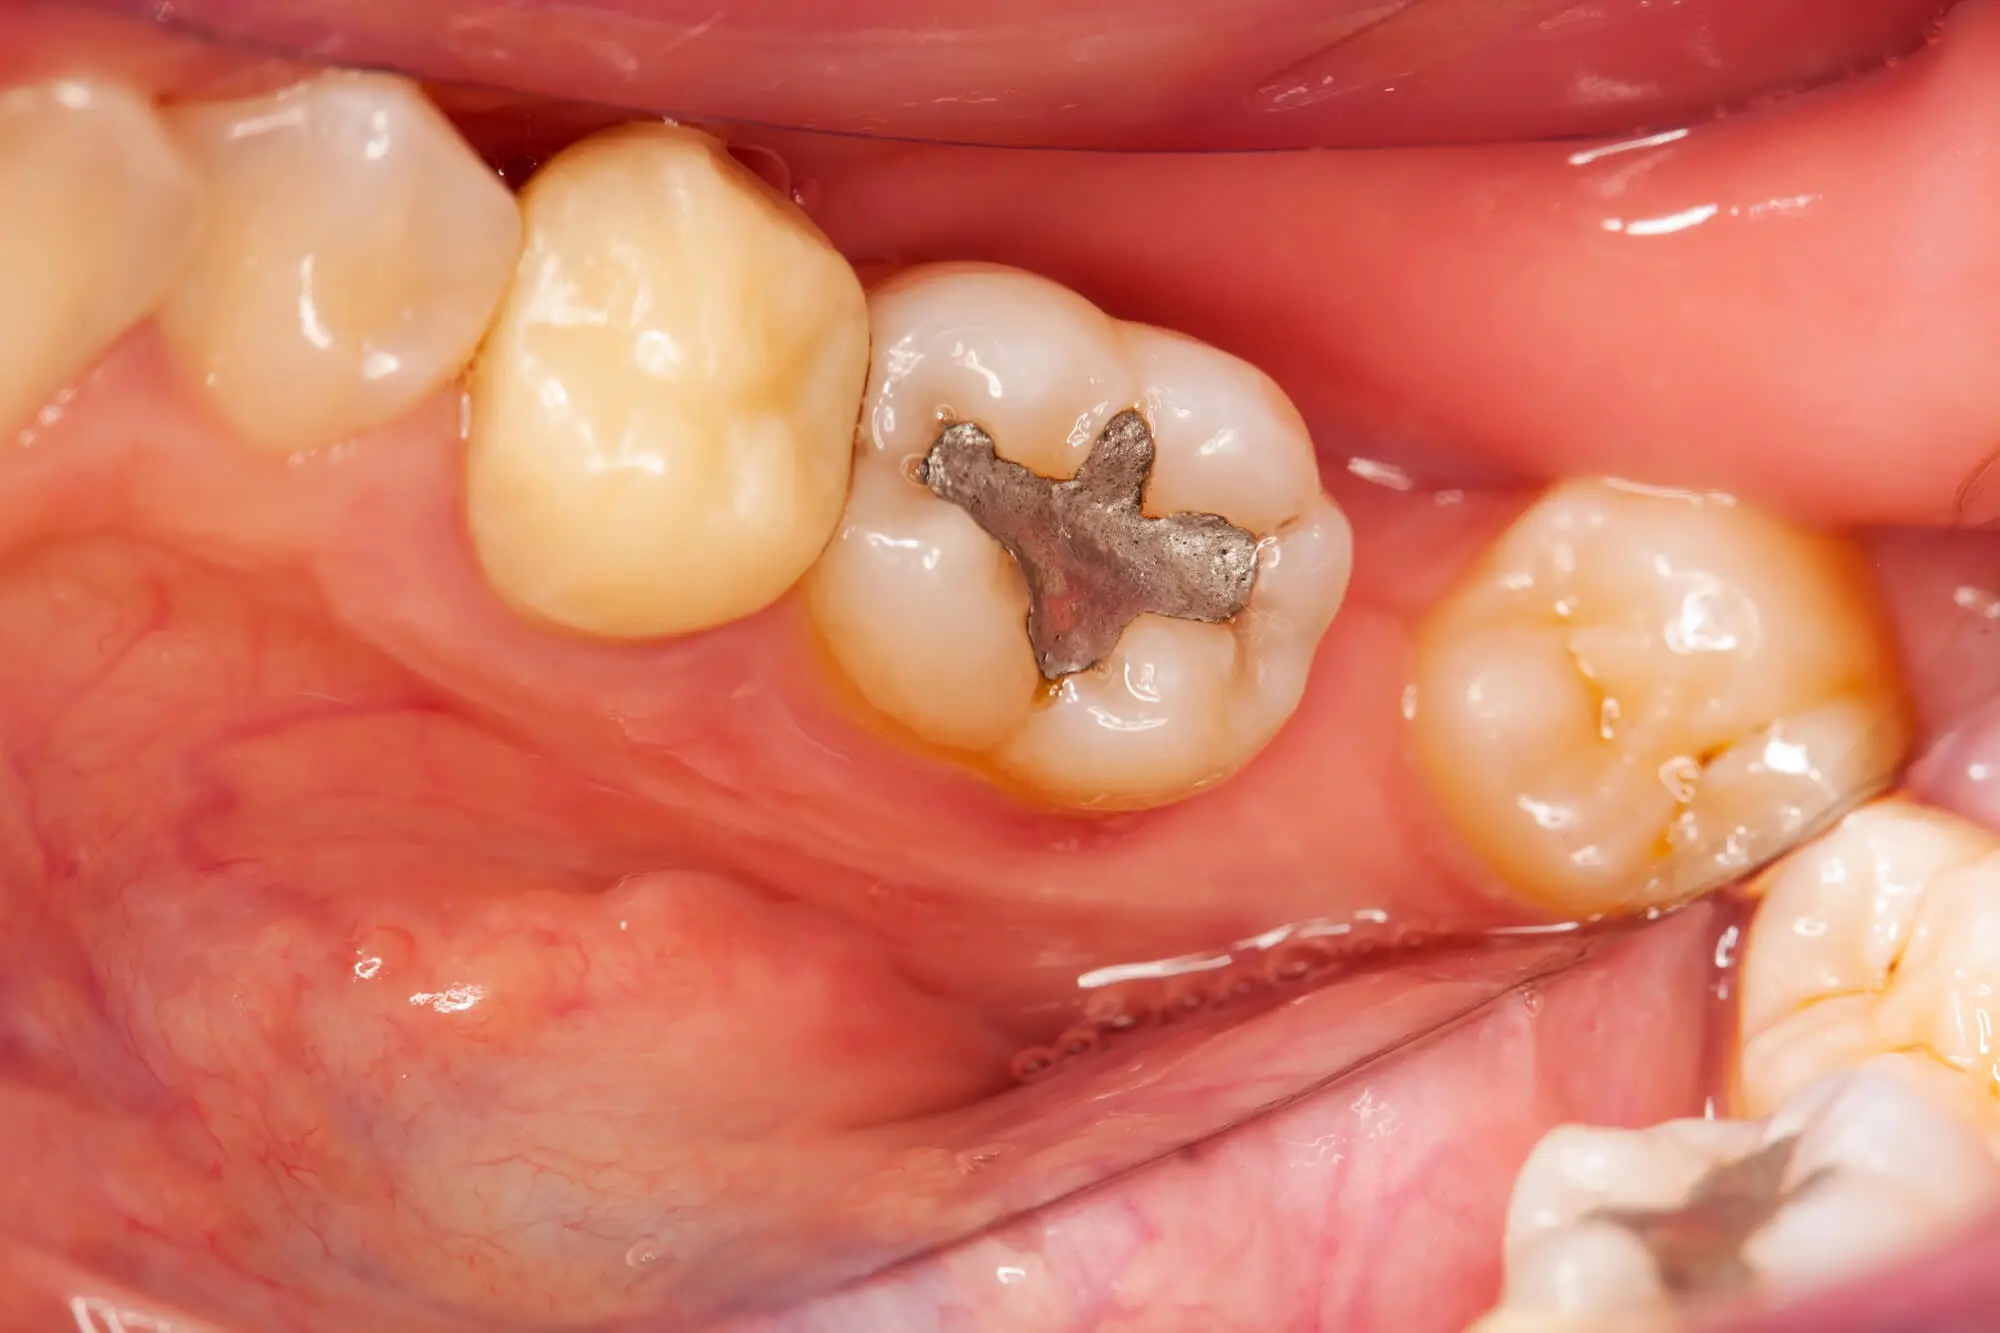

Amalgam fillings are durable, silver-colored dental materials made from a mixture of metals. They’re commonly used for back teeth due to the belief that these metal restorations are more long-lasting and resistant to wear.

Some of the metals contained in amalgam fillings include:

- Mercury (50%): Due to its stability, moldability, and capacity to fuse other metals, mercury is the main ingredient in amalgam fillings. Although mercury is toxic in its pure form, it is considered safe in dental amalgam fillings because it hardens when combined with other powdered metals.

- Silver (22–32%): Silver is added to increase the amalgam mixture's strength and durability. It improves the material's resistance to corrosion and lends the filling its distinctive silver-gray hue.

- Tin (14–30%): Tin makes the amalgam more workable and malleable, facilitating the filling's placement in the cavity. When exposed to temperature changes in the mouth, it also helps the alloy expand and contract without breaking.

- Copper (6–14%): Copper is added to improve the amalgam's strength and resistance to wear. It also lessens the possibility of corrosion, extending the filling's lifespan.

- Other Elements: Trace amounts of palladium, zinc, or other metals may be added to improve the material's qualities even further.